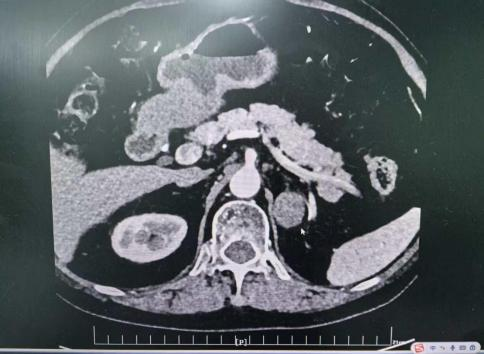

王女士的诊疗充分展现了附属医院在应对此类复杂病症时的专业与精准。她患高血压多年,规律服用多种降压药仍难以控制,还新增尿频尿急症状。文永安主任接诊后,敏锐察觉潜在病因,立即组织团队进行全面评估:细致梳理病史、制定针对性检查方案,最终通过肾上腺CT与内分泌检测,确诊为“肾上腺占位性病变”,且肿瘤有分泌功能,这正是血压居高不下的根源。

明确病因后,手术成为关键。考虑传统开放手术创伤大、恢复慢,结合王女士身体状况,泌尿外科团队决定实施腹腔镜微创手术。术中,凭借娴熟技巧与默契配合,在高清腹腔镜下精准分离肿瘤,最大程度保护周围器官。手术创伤小、出血少,术后王女士血压稳步降至正常,尿频尿急症状消失,无需再依赖多种降压药。